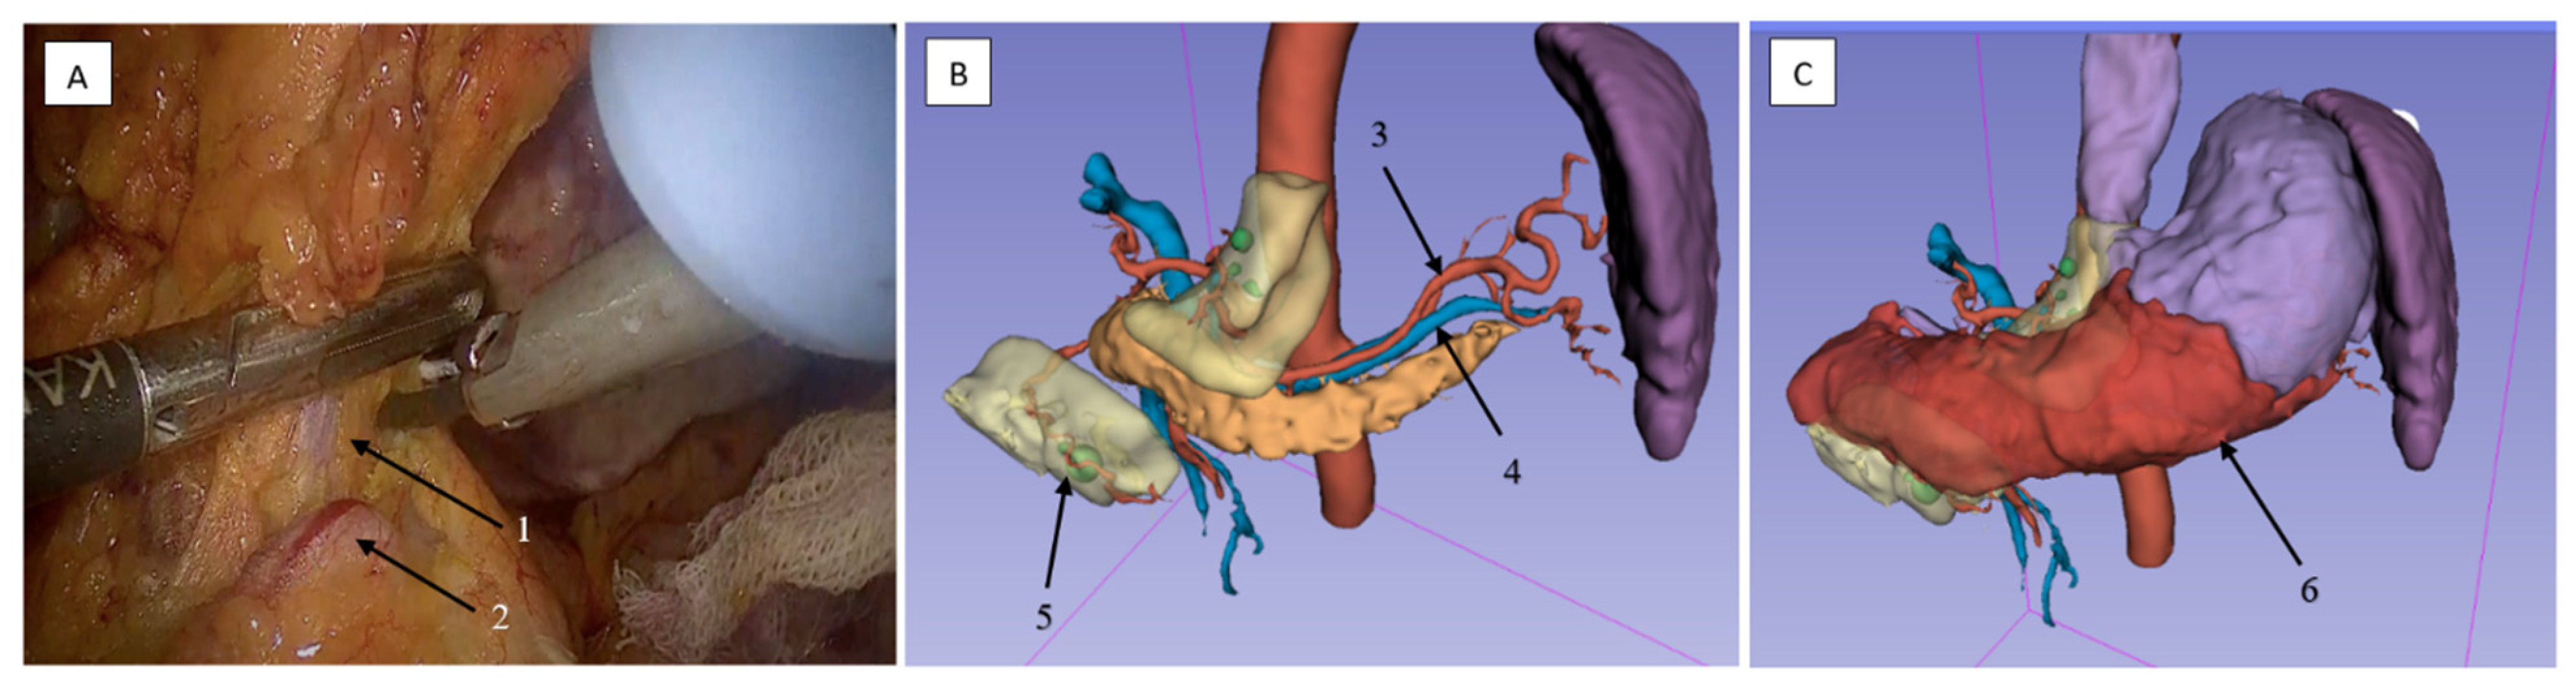

2.3.1. Surgical Dissection Planes and Landmarks: Critical Steps of Gastrectomy in the Embryonic Plane

2.3.2. Lymphadenectomy of the Greater Omentum and Left Gastroepiploic Vascular Territory (Stations 4sb and 4d)

2.3.3. Lymphadenectomy of Stations 11p/11d and 10 (Splenic Artery and Hilar Nodes)

2.3.4. Lymphadenectomy of Stations 4sb and 6 Was Performed

2.3.5. Lymphadenectomy of Stations 5 (Suprapyloric) and 12a (Hepatoduodenal Ligament)